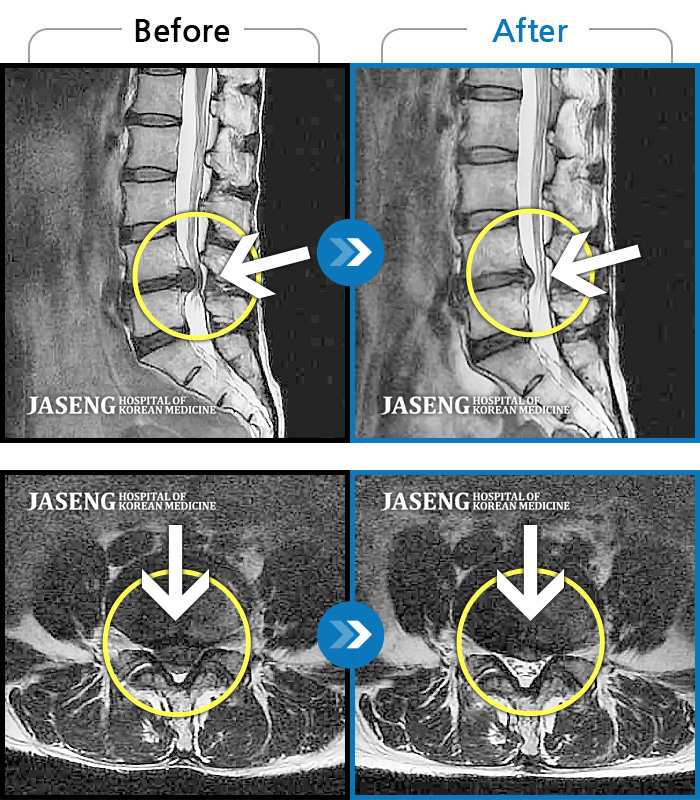

허리디스크

수원 · 김태성 원장

우측 허리 통증과 우측 다리 방사통으로 활동하기 힘든 상태

촬영시기

2021.02.03 ~ 2021.07.09

2022.03.25